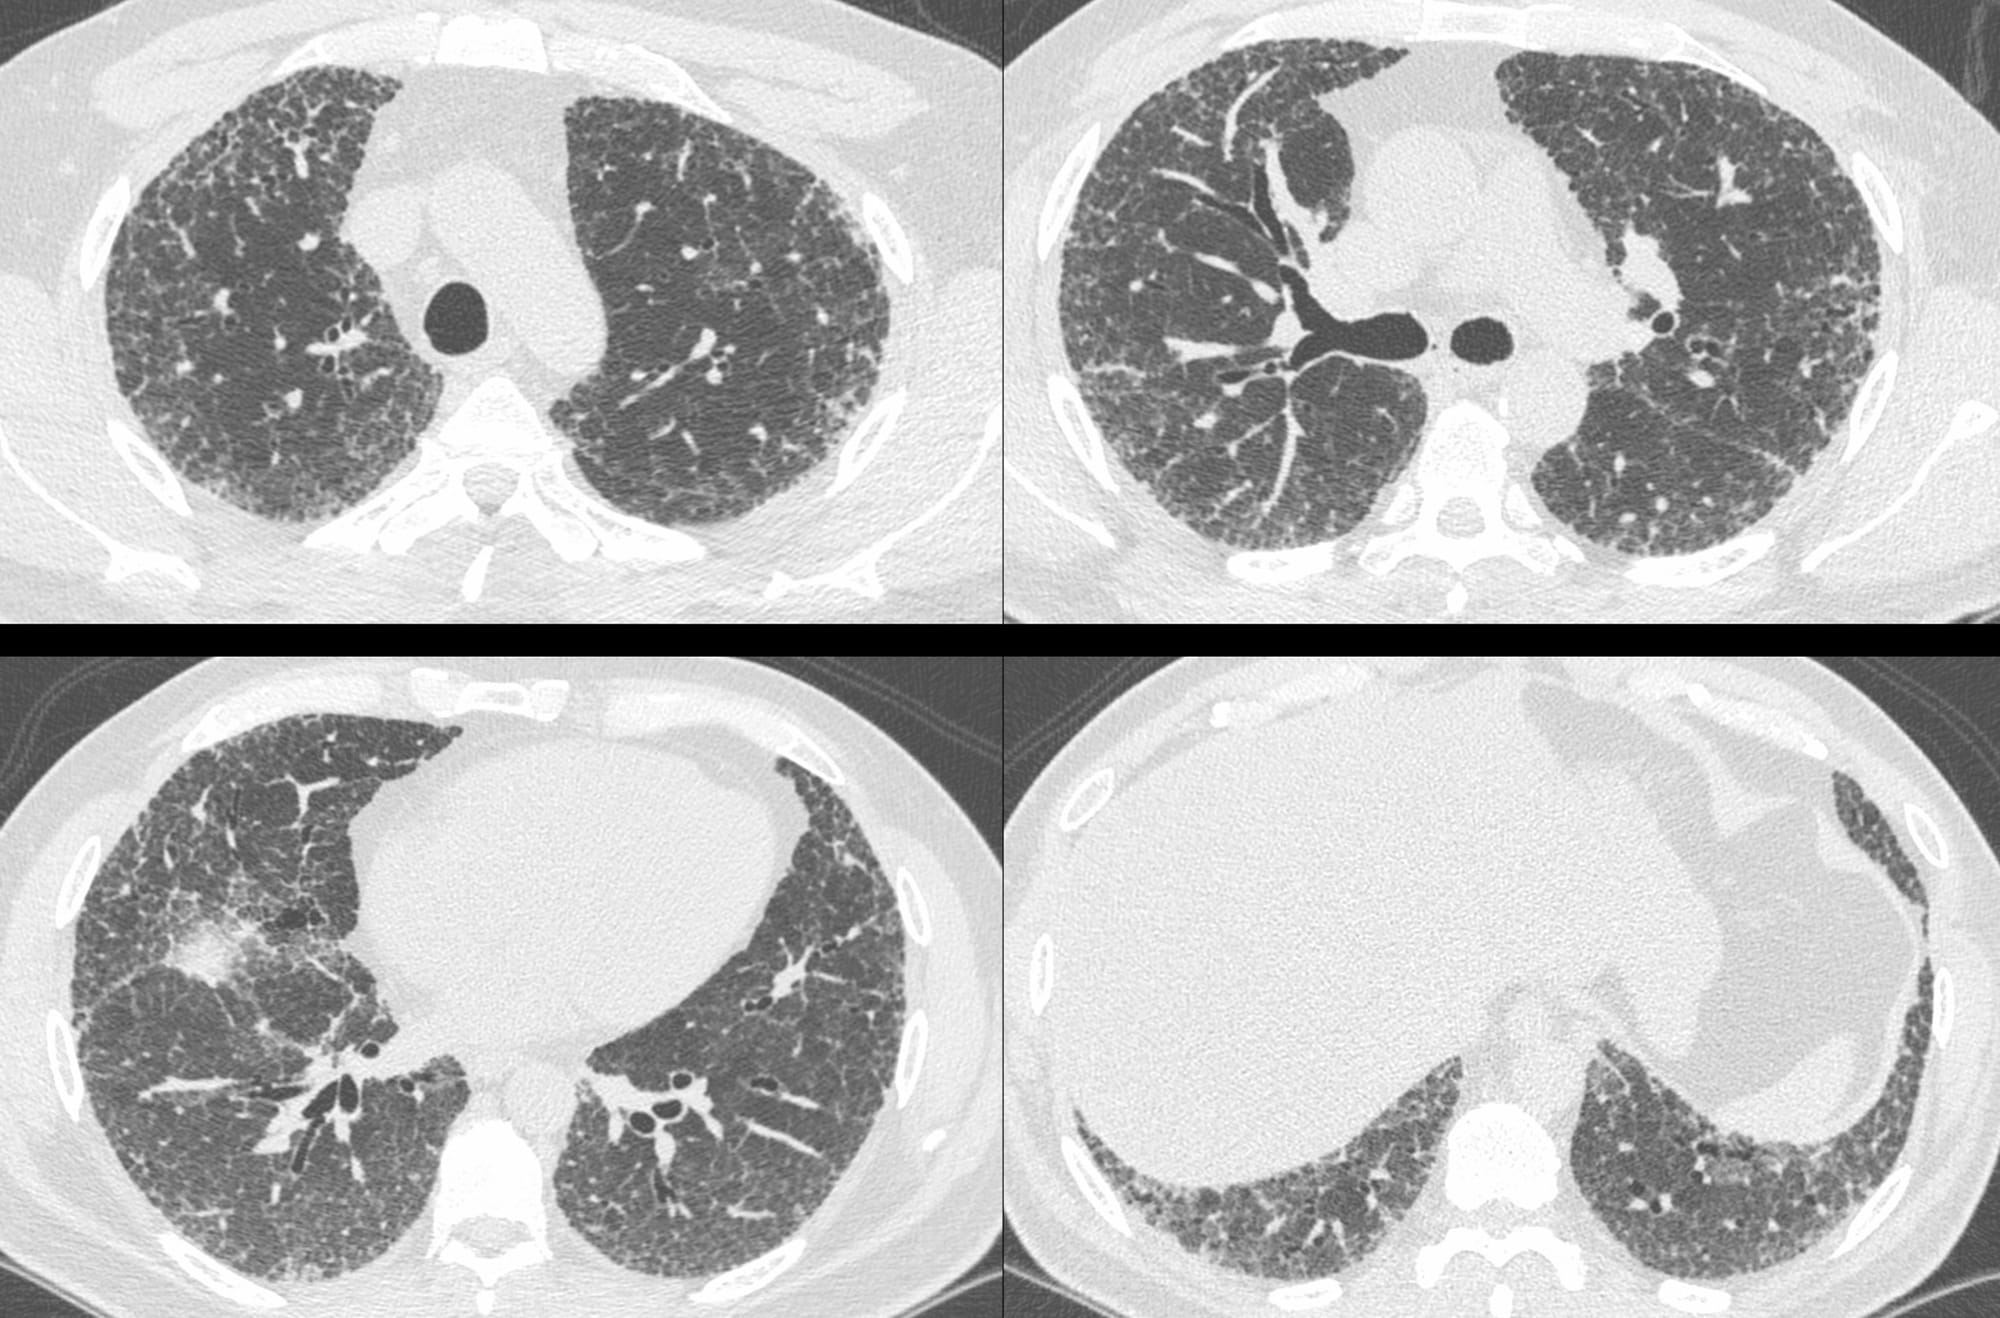

A 52-years old man presented with a probable UIP pattern in 2018.

At this age, this is indistinguisable from a fibrotic NSIP pattern. He was a non-smoker and had no etiology including connective tissue disease (CTD).